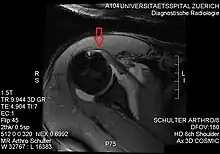

Imaging

MRI. Partial rupture of the cranial subscapularis tendon at the insertion site

There is no singularly imaging device or technique for a satisfying and complete subscapularis examination, but rather the combination of the sagittal oblique MRI / short-axis US and axial MRI / long-axis US planes seems to generate useful results. Additionally, lesser tuberosity bony changes have been associated with subscapularis tendon tears. Findings with cysts seem to be more specific and combined findings with cortical irregularities more sensitive.[5]